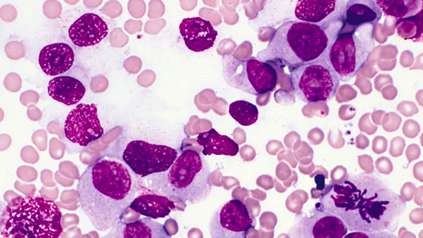

Science and Innovation

At the Wellcome Genome Campus we undertake both wet and dry lab science, basic research and the delivery of bioinformatics resources for the global scientific community.